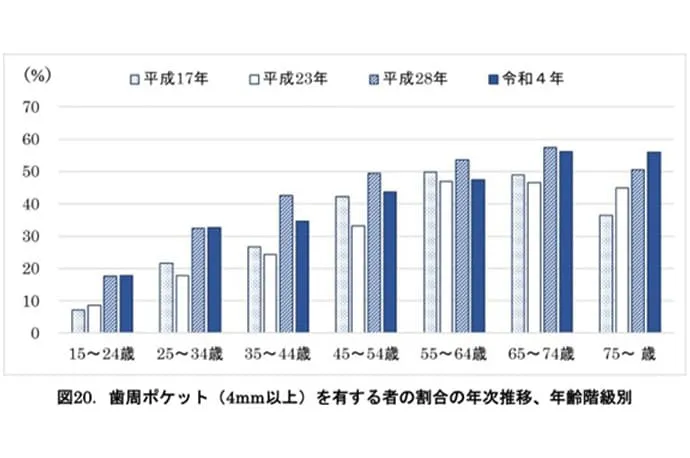

2018年の8020推進財団の調査では、歯を失う原因として最も多いのが歯周病であることが明らかになりました。また、2022年の歯科疾患実態調査によると、25歳以上の約30%が歯周病に罹患しており、45歳以上では40%以上、65歳以上では50%以上にのぼると報告されています。

令和4年歯科疾患実態調査の結果(概要)(厚生労働省)より引用

令和4年歯科疾患実態調査の結果(概要)(厚生労働省)より引用

令和4年歯科疾患実態調査の結果(概要)(厚生労働省)より引用

歯は顎の骨によって支えられています。歯と歯ぐきの間には「歯周ポケット」と呼ばれるすき間があり、健康な状態では深さは3mm以下です。

しかし、歯ぐきに炎症が起きたり、歯を支える骨が破壊されている場合には、歯周ポケットが4mm以上に深くなります。まずはこの歯周ポケットの状態を詳しく検査します。